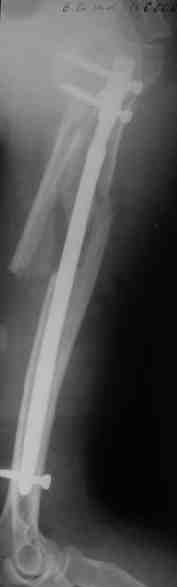

Прооперировали больную с переломом плеча все же гвоздем, Фото в приложении.

Интересно, а канал рассверливали?

Гвоздик похоже ЦИТОвский?

Полагаю, бабушку можно поздравить с обретением

независимости. Судя по снимкам, неврологических расстройств нет и такая пациентка выпишется после снятия швов.

Немножко уточню ответы Максима.

Только сформировали канал в головке. Диафиз не рассверливали. Хотя при необходимости, конечно, рассверлили бы.

НЗ> Гвоздик похоже ЦИТОвский?

Гвоздь большеберцовый нашей модификации, действительно, их делает предпричятие "ЦИТО". Тут взят 9 мм, укорочен до 240 мм, сделано дополнительное отверстие самое проксимальное, ну и для дистального винта.

Неврологии нет, а выписать можно хоть на второй день, швы можно снять и в местной больнице.

Почему так надолго? На ближэайшие недели - разработка движений, и все. Полагаю, что недель после 4 никаких рекомендаций не будет нужно, просто жить обычной жизнью сельской пенсионерки.